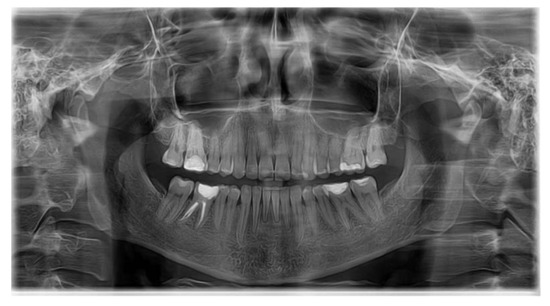

| SNA | 80.03 | 81.08 | 3.7 | Normal A-P position of the maxilla |

| SNB | 75.40 | 79.17 | 3.8 | Normal A-P position of the mandible |

| ANB | 2.46 | 4.63 | 1.8 | skeletal class II |

| FMA | 26.32 | 29.63 | 3.0 | Hypodivergent facial pattern |

| Gonial angle | 123.44 | 124.31 | 5.4 | Normal gonial angle |

| APDI | 74.22 | 85.74 | 4.0 | Skeletal class II |

| A to N-Perp (FH) | −2.58 | 0.4 | 2.3 | Retruded maxilla |

| B to N-Perp (FH) | −12.06 | −3.5 | 2.0 | Retruded mandible |

| Pog to N-Perp (FH) | −9.14 | −1.8 | 2.5 | Retruded chin point |

| FH to AB | 76.26 | 81 | 3.0 | Skeletal class II |

| A-B to mandibular plane | 77.41 | 69.3 | 2.5 | Large angle |

| Wits appraisal | 5.61 | −2.74 | 0.3 | Skeletal class II |

| Overjet | 4.79 | 2 | 2.0 | Large overjet |

| Overbite | 2.46 | 2 | 2.0 | Normal overbite |

| U1 to FH | 100.88 | 113.8 | 6.4 | Retroclined upper incisor |

| U1 to SN | 93.59 | 105.28 | 6.6 | Retroclined upper incisor |

| U1 to UOP | 70.28 | 55 | 4.0 | Retroclined upper incisor |

| IMPA | 80.50 | 91.62 | 3.2 | Retroclined lower incisor |

| L1 to LOP | 74.77 | 66 | 5.0 | Retroclined lower incisor |

| Interincisal angle | 152.29 | 128 | 5.3 | Uprighted interincisal angle |

| Cant of occlusal plane | 5.66 | 9.3 | 3.8 | Normal occlusal plane angle |

| U1 to NA(mm) | 0.10 | 4 | 3.0 | Retruded upper incisor |

| U1 to NA(deg) | 13.55 | 22 | 5.0 | Retroclined upper incisor |

| L1 to NB(mm) | 1.5 | 4 | 2.0 | Retruded lower incisor |

| L1 to NB(deg) | 9.52 | 25 | 5.0 | Retroclined lower incisor |

| Upper incisal display | 3.17 | 2.5 | 1.5 | Normal incisal display |

| Upper lip to E-plane | −3.42 | 0 | 2.0 | Retruded upper lip |

| Lower lip to E-plane | −2.22 | 0 | 2.0 | Retruded lower lip |

| Nasolabial angle | 114.84 | 95 | 5.0 | Retruded lip |

| Extraction Index | 159.69 | 153.8 | 7.8 | Normal |